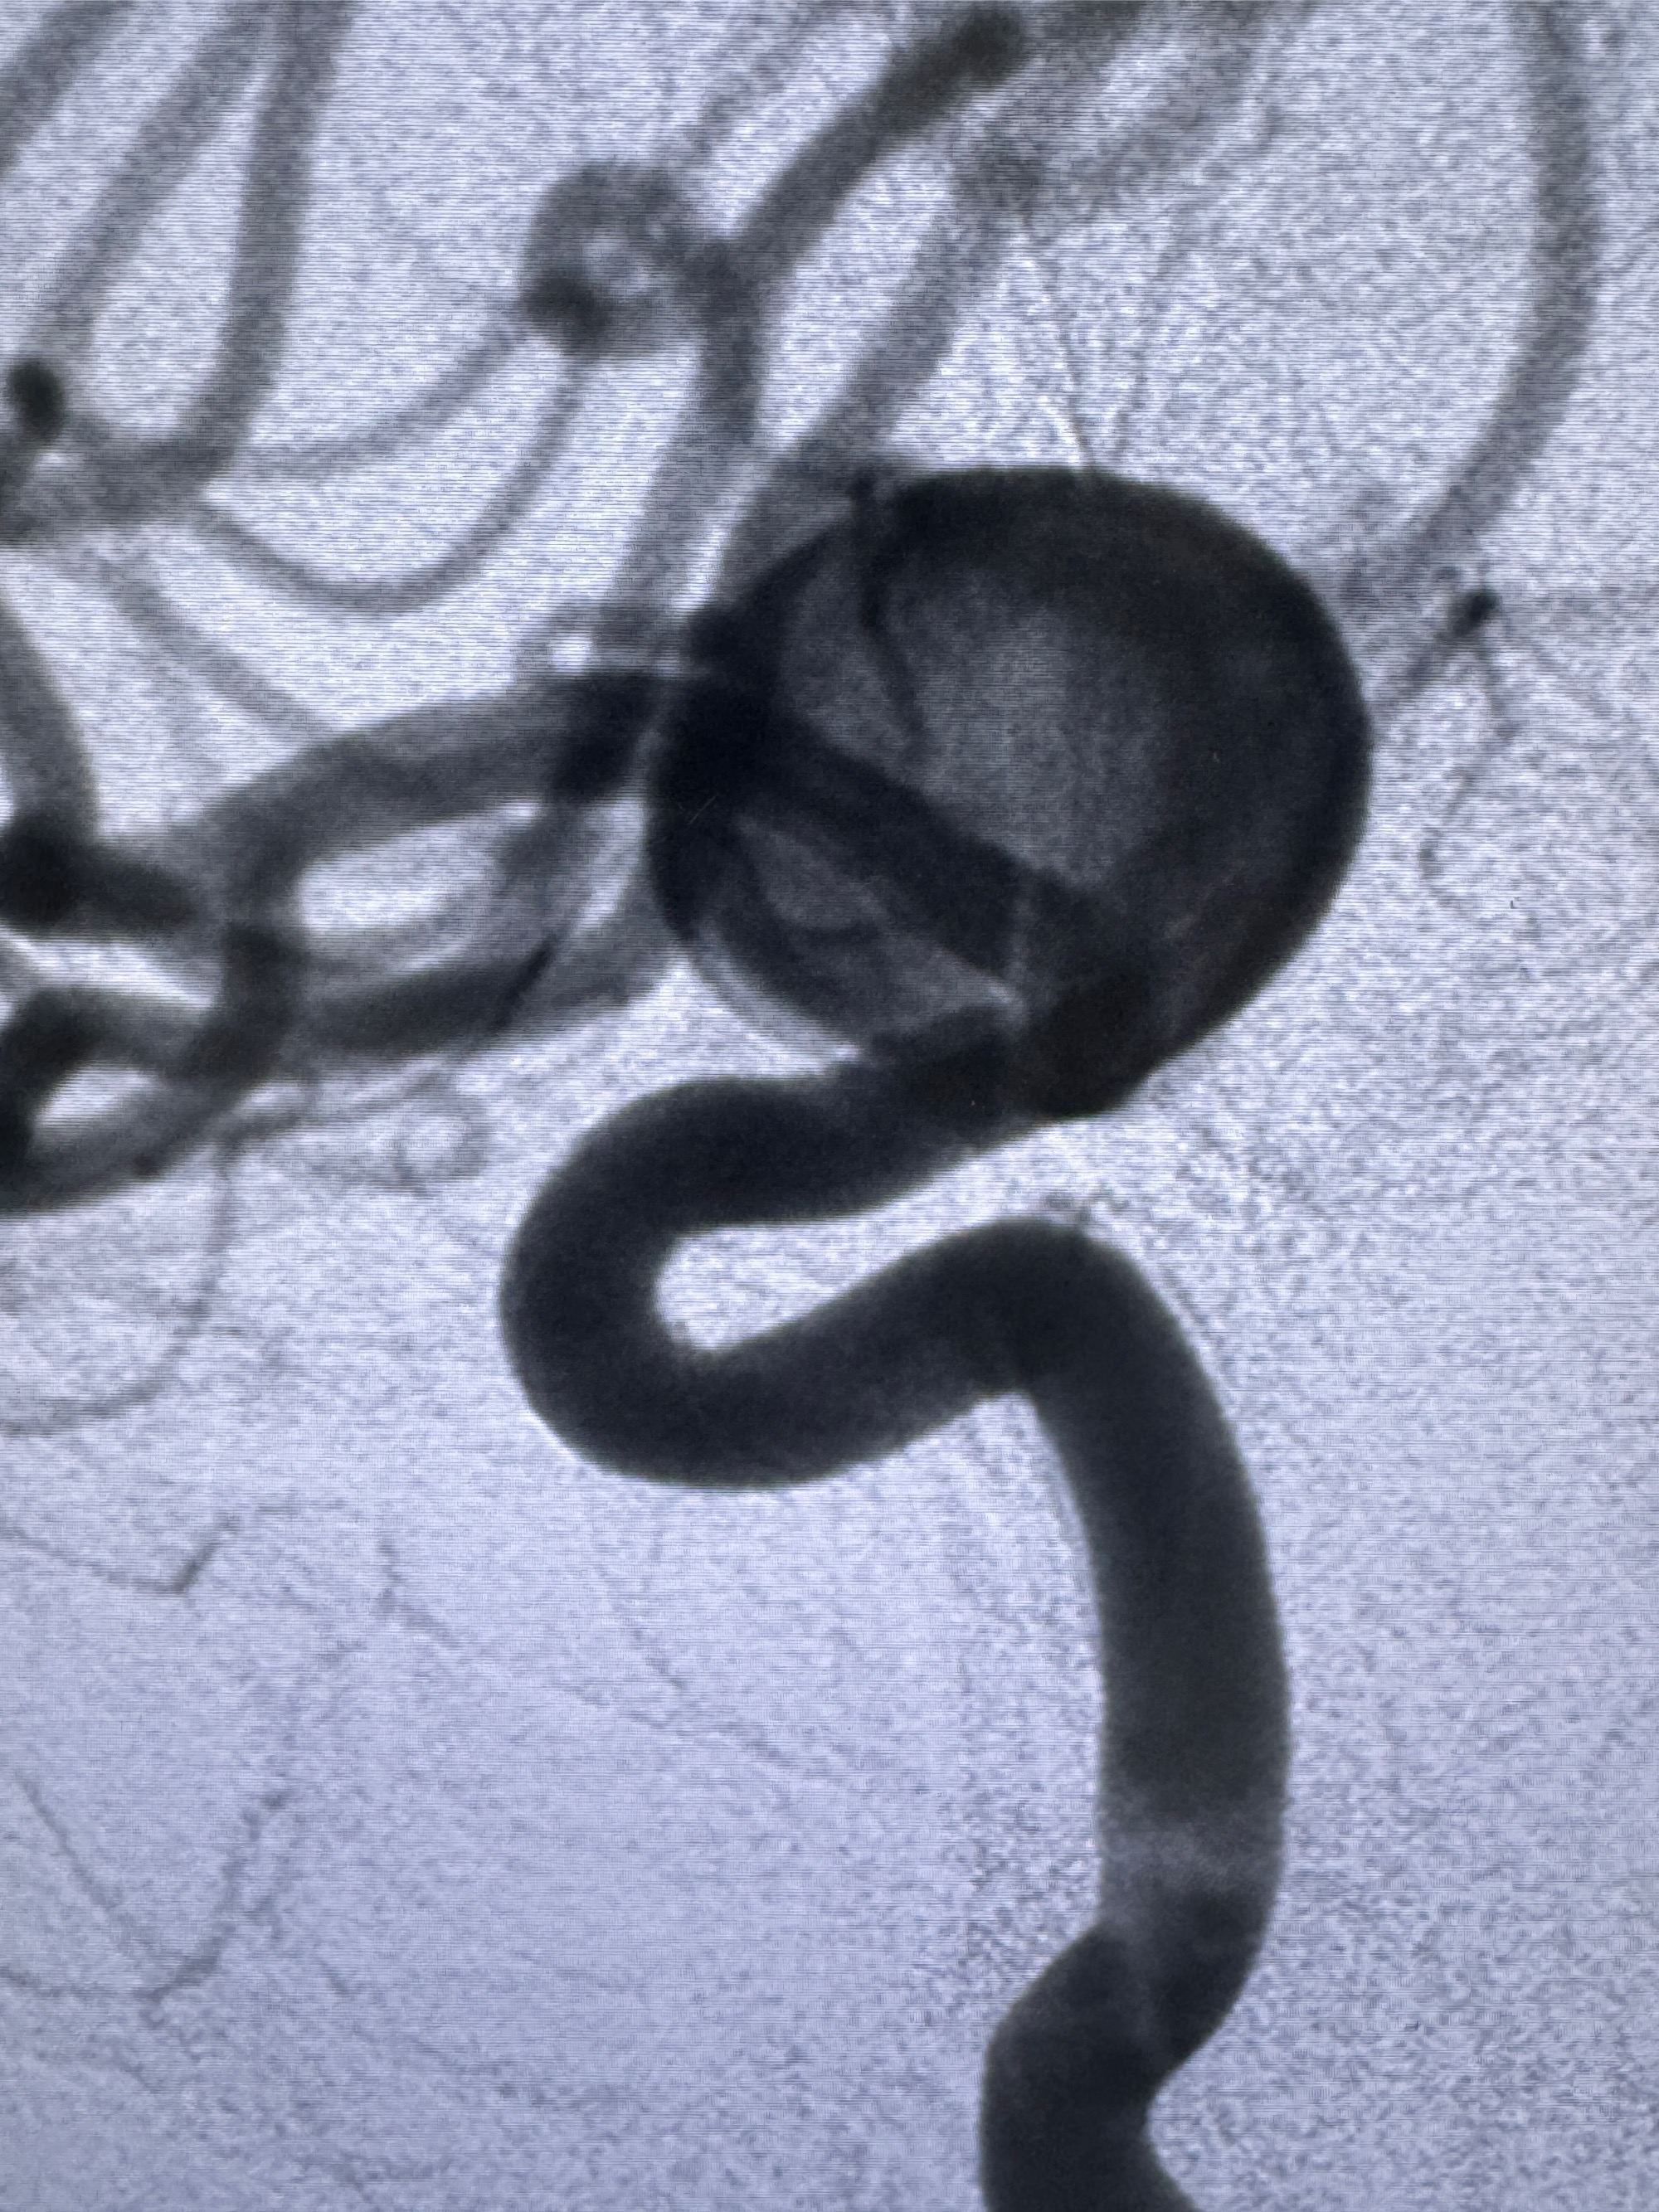

造影显示支架贴壁情况

再次造影确认支架贴壁情况

看动脉瘤内造影剂滞留,未见明确射流,遂撤出预留的栓塞微导管,快速结束手术,经导引导管灌注替罗非班250ug。

2023-12-27术后第十天复查DSA

支架贴壁佳,但可见射流,咋办?

支架植入顺利,贴壁佳,支架内血流通畅,动脉瘤内血液滞留明显